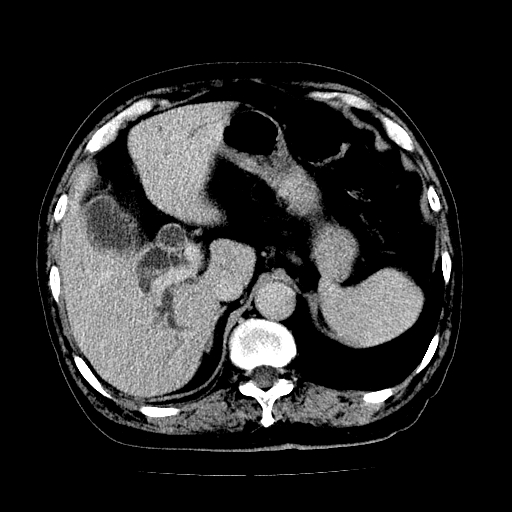

男,71岁,皮肤黄染四天。

肝内外胆管及胆总管上段扩张,考虑为梗阻所致,建议mrcp检查。

考虑胆总管癌并肝内外胆管扩张。

胆管癌并肝内外胆管扩张。

支持考虑胆总管癌并肝内外胆管扩张。 局部应薄扫。心包钙化。

胰腺上端胆总管内见软组织影,强化不明显,结合临床,还是考虑低位梗阻性黄疸,胆总管癌可能性大